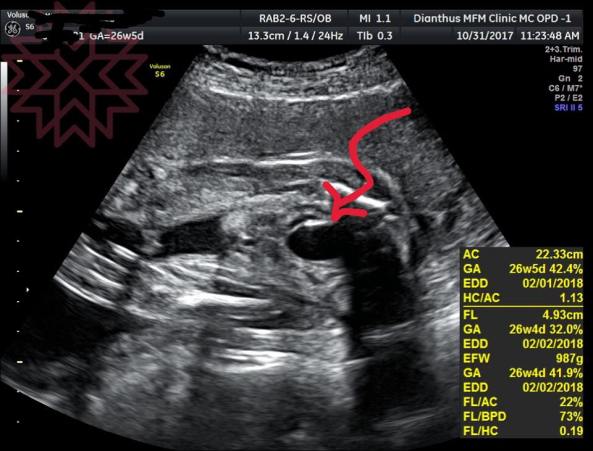

超音波照片中箭頭指的黑色那一團顯示的是胎兒膀胱

他正快樂的工作著呢

停藥之後

代表著腎臟功能已經完全恢復

再也沒有受到藥物作用的抑制

羊水也完全恢復正常